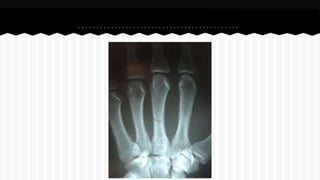

RESPONDA O NOME DO OSSO EM QUE

SE ENCONTRA A (S) FRATURA (A).